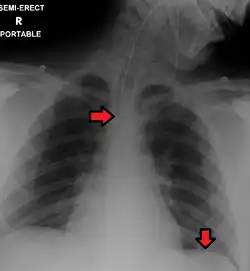

Confirming placement

It is necessary to confirm placement of the endotracheal tube to ensure that the tube is properly positioned within the trachea and has not accidentally passed into the esophagus instead. Additionally, it is important to confirm that the endotracheal tube was not placed too deep in the trachea where is may only be ventilating one of the lungs due to it being positioned within a mainstem bronchi (frequently the right mainstem bronchi due to a more obtuse angle than the left). The gold standard for confirming successful placement of an endotracheal tube is direct visualization of the tube passing through the vocal cords and positive end-tidal carbon dioxide on capnography. Secondary methods of confirmation include oxygen saturation, chest x-ray, ultrasound, condensation in the endotracheal tube, equal chest rise, breath sounds heard on both sides of the chest (often with the assistance of a large tidal volume breath), and an absence of breath sounds over the epigastrium. No single method of confirming placement is 100% reliable so multiple methods of confirmation should be utilized.[6][17][18]